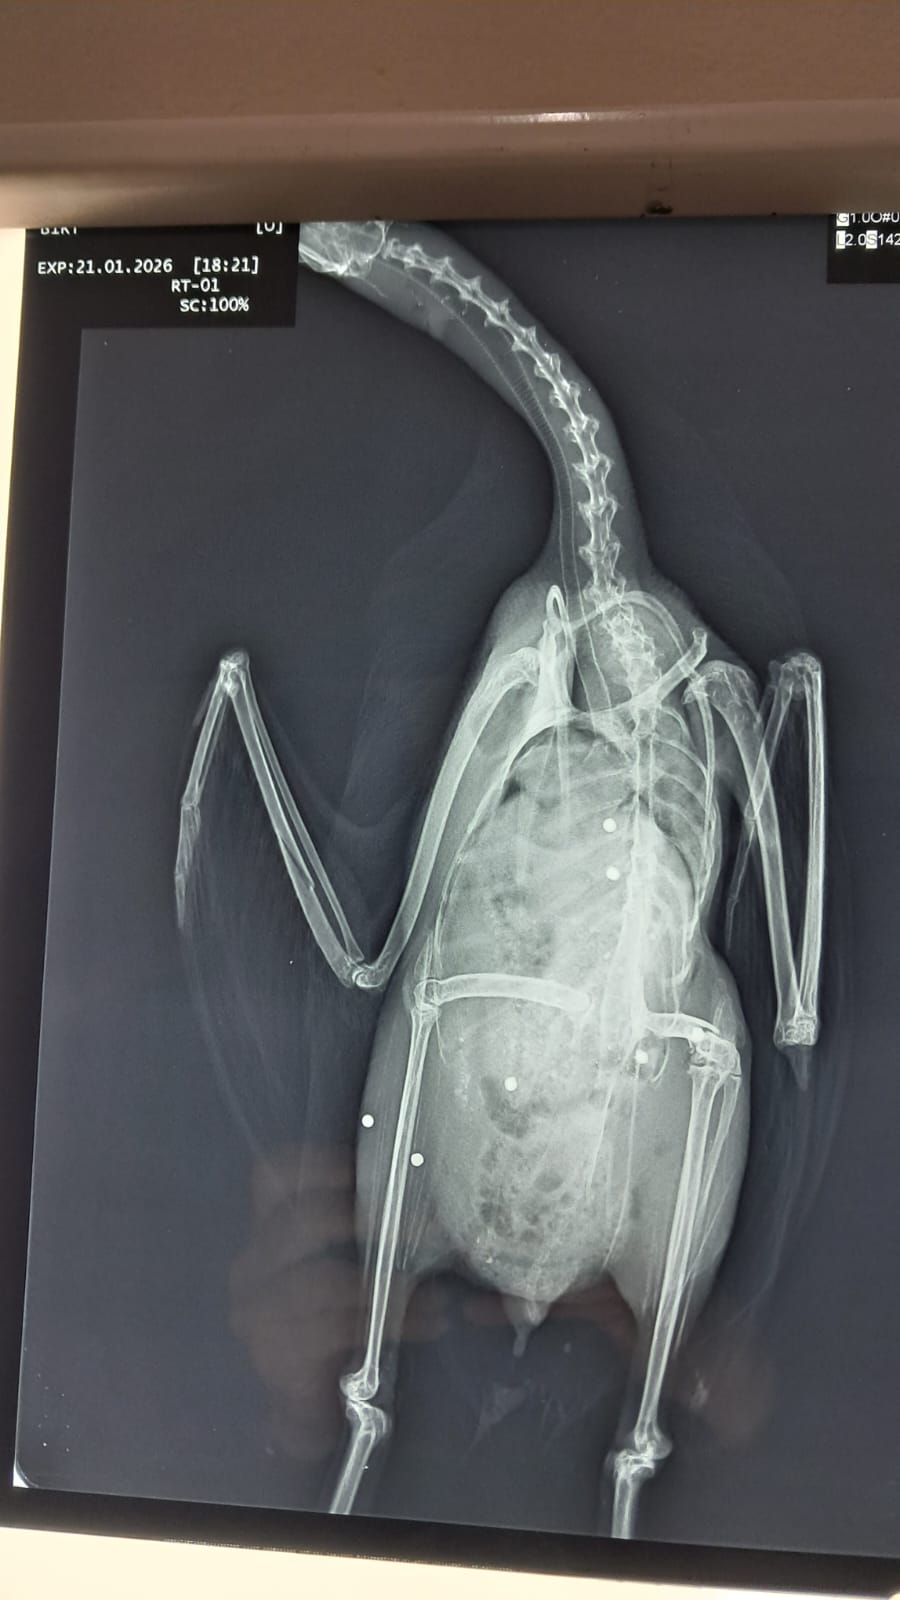

Το περιστατικό αποκτά ιδιαίτερη βαρύτητα καθώς, σύμφωνα με τις ίδιες πληροφορίες, στη λίμνη είχε παραμείνει τους τελευταίους μήνες ένα φλαμίνγκο που δεν είχε καταφέρει να συνεχίσει τη μεταναστευτική του πορεία και παρακολουθούνταν συστηματικά από εθελοντές. Κατά την επίσκεψη, το φλαμίνγκο δεν εντοπίστηκε, εντοπίστηκαν όμως στην επιφάνεια του νερού δύο νεκρά μαυροβουτηχτάρια και ένα ακόμη βαριά τραυματισμένο, το οποίο τελικά κατέληξε. Όπως φαίνεται και από τις φωτογραφίες που δόθηκαν στη δημοσιότητα, ο ακτινογραφικός έλεγχος απέδειξε την ύπαρξη σκαγιών στο σώμα του τραυματισμένου πτηνού. Το μαυροβουτηχτάρι αποτελεί προστατευόμενο και μη θηρεύσιμο είδος, γεγονός που καθιστά τη θανάτωσή του παράνομη και επιφέρει βαριές κυρώσεις.